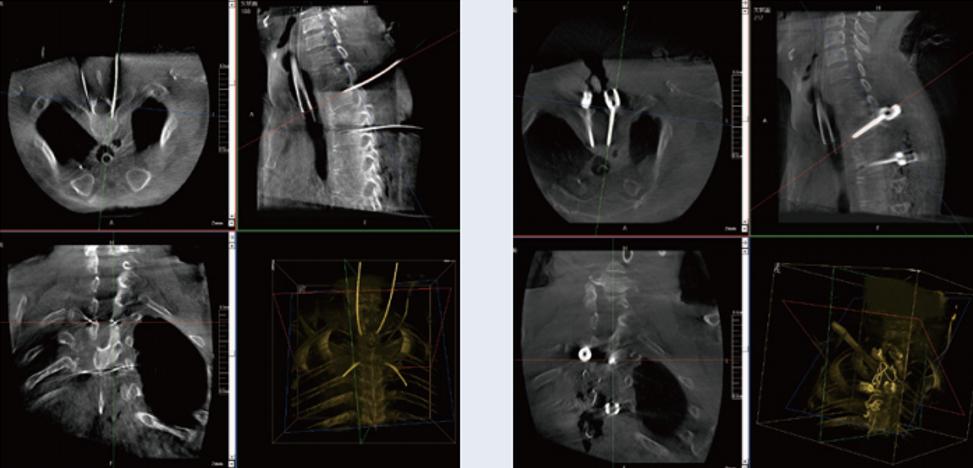

螺釘規(guī)劃后的圖像

植入螺釘后的圖像

術(shù)中三維C形臂與脊柱導(dǎo)航機器人配合應(yīng)用,實現(xiàn)準確定位,確保了手術(shù)安全、高效完成。術(shù)后二維、三維影像顯示手術(shù)效果良好,達到預(yù)期目的。